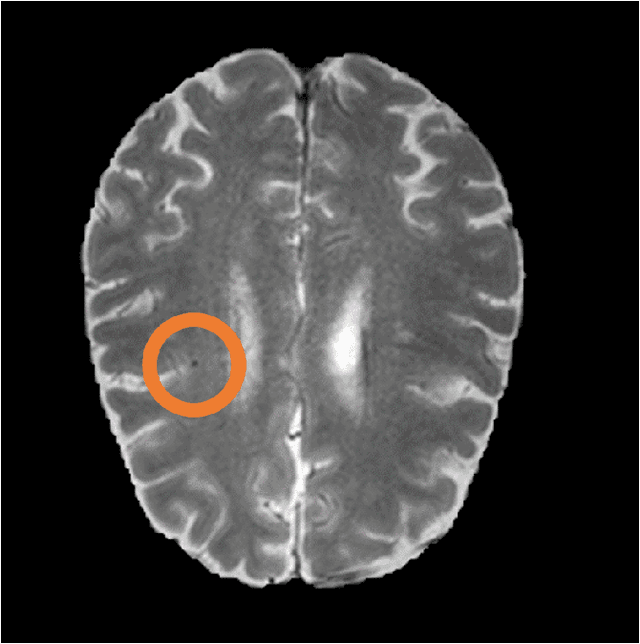

Abstract:Cerebral microbleeds are small, dark, round lesions that can be visualised on T2*-weighted MRI or other sequences sensitive to susceptibility effects. In this work, we propose a multi-stage approach to both microbleed detection and segmentation. First, possible microbleed locations are detected with a Mask R-CNN technique. Second, at each possible microbleed location, a simple U-Net performs the final segmentation. This work used the 72 subjects as training data provided by the "Where is VALDO?" challenge of MICCAI 2021.

Abstract:Cerebral microbleeds are small hypointense lesions visible on magnetic resonance imaging (MRI) with gradient echo, T2*, or susceptibility weighted (SWI) imaging. Assessment of cerebral microbleeds is mostly performed by visual inspection. The past decade has seen the rise of semi-automatic tools to assist with rating and more recently fully automatic tools for microbleed detection. In this work, we explore the use of nnU-Net as a fully automated tool for microbleed segmentation. Data was provided by the ``Where is VALDO?'' challenge of MICCAI 2021. The final method consists of nnU-Net in the ``3D full resolution U-Net'' configuration trained on all data (fold = `all'). No post-processing options of nnU-Net were used. Self-evaluation on the training data showed an estimated Dice of 0.80, false discovery rate of 0.16, and false negative rate of 0.15. Final evaluation on the test set of the VALDO challenge is pending. Visual inspection of the results showed that most of the reported false positives could be an actual microbleed that might have been missed during visual rating. Source code is available at: https://github.com/hjkuijf/MixMicrobleedNet . The docker container hjkuijf/mixmicrobleednet can be pulled from https://hub.docker.com/r/hjkuijf/mixmicrobleednet .